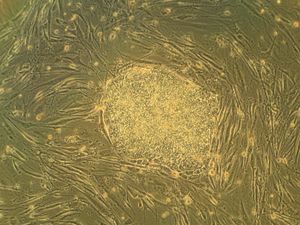

image الإنجليزية

Humanstemcell.JPG

٣٬٠٧٢ × ٢٬٣٠٤؛ ٢٫٤١ ميجابايت